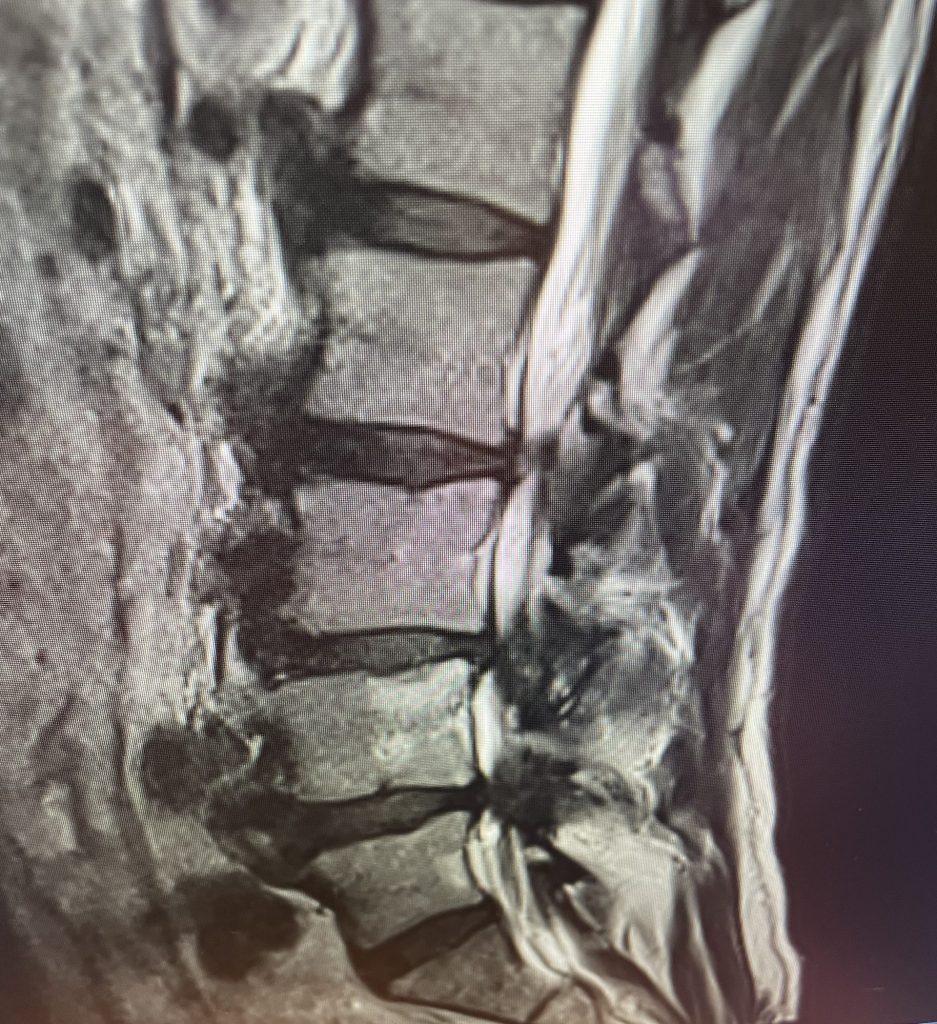

This 71 year-old male presents with a long history of progressive pain in the low back with radiation to both legs in the anterior thigh distribution, the left being worse than the right. He feels that his legs get weak. Standing and walking worsen the low back pain and lower extremity symptoms while sitting relieves the symptoms. He failed PT and epidural injections. Imaging studies revealed severe lateral recess stenosis do mainly to severed thickened ligament. He had severe lateral recess stenosis from L2-5 (Fig 4) as well as central stenosis. He also had a slight retrolisthesis at L3-4 and L4-5. He had on the left in particular a very enlarged protruded segment of thickened ligamentum in the subarticular recess at L3-4 (Fig 5) which was likely responsible for his left leg pain as the patient had symptoms of an L4-type syndrome. It was decided to perform a decompressive laminectomy from L2-5. Because of retrolisthesis it was decided to perform a noninstrumented onlay bone fusion or an in situ fusion from L3-5. In this case it was very important to decompress not only the thecal sac, but also the lateral recess with the thickened ligament at the point where the nerve makes its course into the forman. As a surgeon you must really undercut the facet joints to clear the lateral recess and feel how the nerve root with one’s instrument is being released as it enters the foramen. Postoperatively the patient had resolution of his leg pain, particularly on the left. In this case the most significant pathology was in the left L3-4 lateral recess, his symptoms and MRI findings correlated well which leads to the most successful operations.

Figure 5: Axial T2-weighted MRI demonstrating severe bilateral lateral recess stenosis secondary to thickened ligamentum flavum. Notice the prominence of the left ligamentum in the subarticular recess.